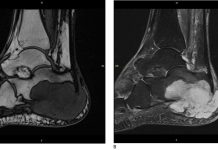

Voetamputatie als fasciitis plantaris kanker blijkt te zijn

Een 79-jarige vrouw in Engeland had pijn in haar rechtervoet. Haar huisarts diagnosticeerde het als fasciitis plantaris (‘hielspoor’). Maar toen de pijn na twee jaar nog niet was verdwenen, bleek ze kanker te hebben. Haar onderbeen moest worden geamputeerd.